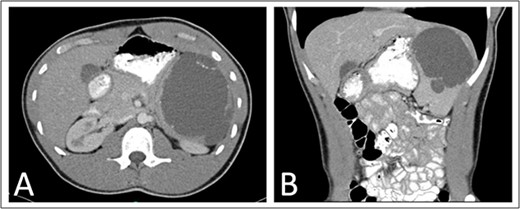

He was seen at 1, 6, and 12 months following surgery without complaints. A 1-year interval abdominal CT (Fig. 3) showed several 3–6 mm nodules in the left upper quadrant near the splenectomy site with the differential including several small lymph nodes, tiny splenules, or neoplastic implants that will be followed with another 1-year interval CT scan.

One year post operative abdominal CT scan (A) axial and (B) coronal abdominal CT images showing several sub-centimeter nodules in the post-splenectomy bed (arrows).